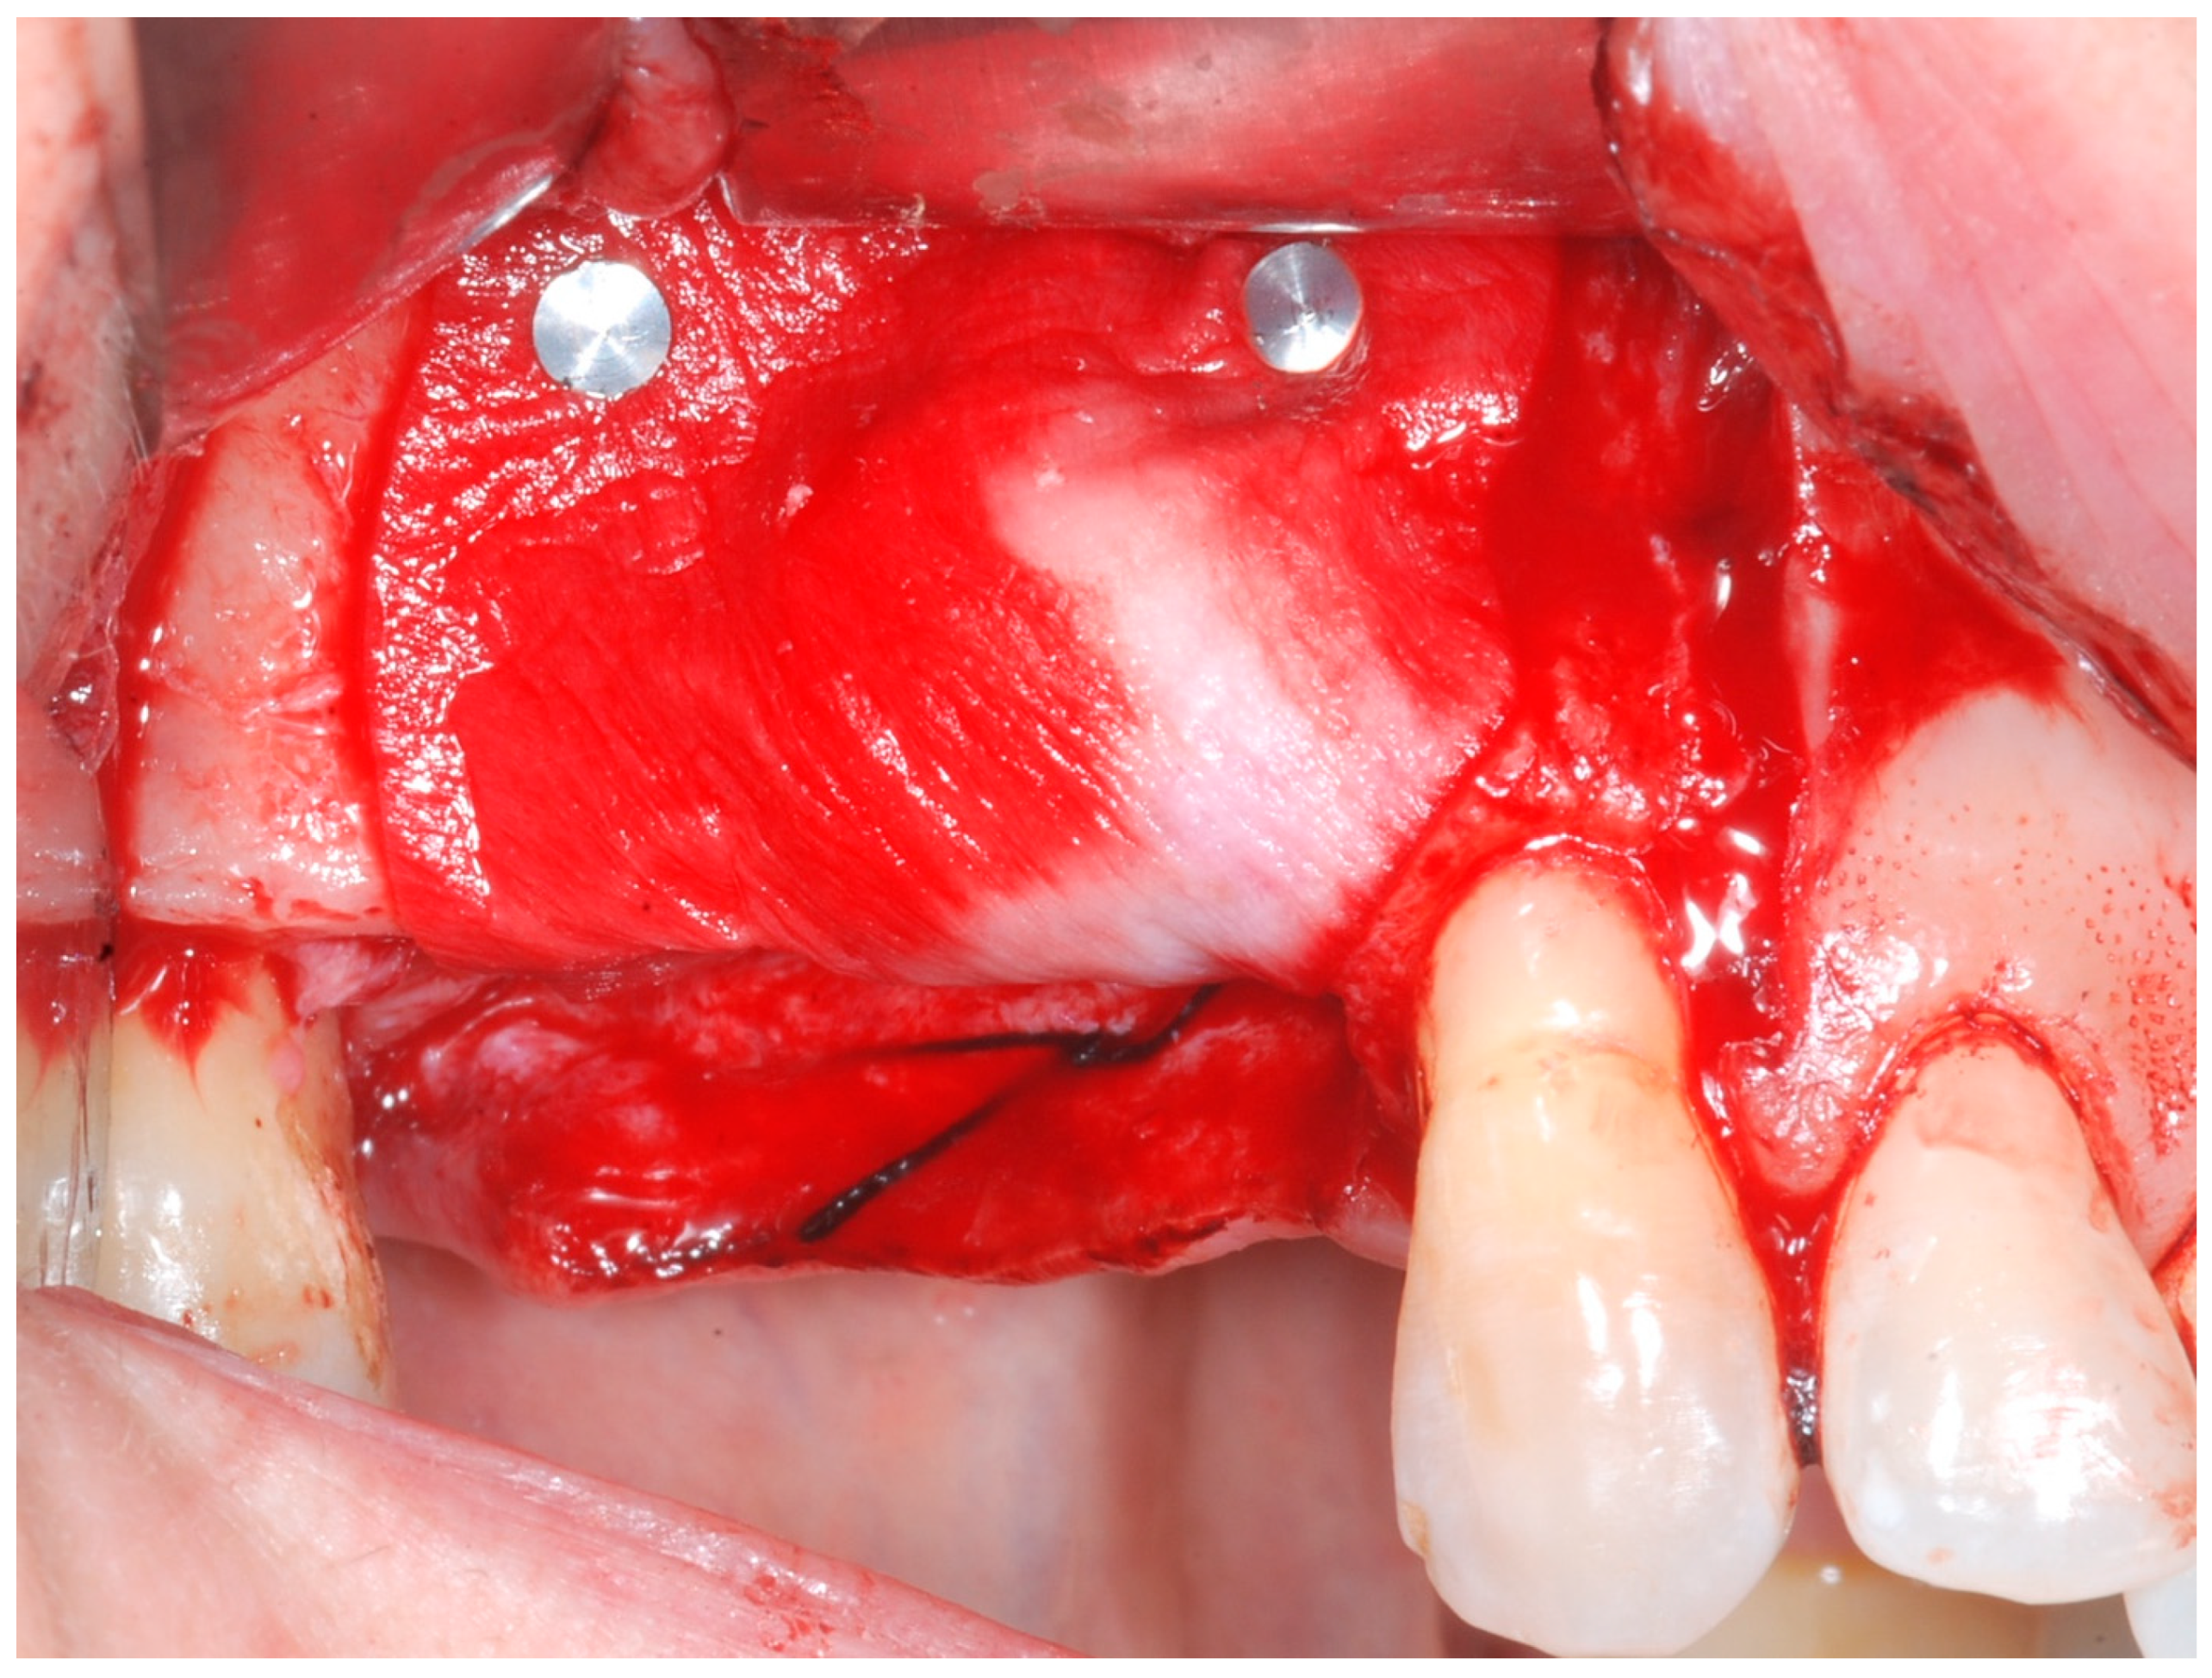

The cortical bone plate was perforated at numerous locations using a round bur in order to allow access of the cells from the bone and bone marrow to the area of regeneration. Subsequently, granules of cancellous deproteinized bovine bone mineral (DBBM) (Bio-Oss, Geistlich AG, Wolhusen, Switzerland), were placed in the defect area (Figure 5). A collagenous resorbable membrane (T-Gen, HYUNDAI BIOLAND Co., Ltd., 162, Gwahaksaneop 3-ro, Ochang-eup, Cheongwon-gu, Cheongju-si, Chungcheongbuk-do, 28125, Republic of Korea) was shaped and trimmed to cover the graft and to extend 2–3 mm onto the intact bony borders of the defect. The membrane was hydrated and the fixation was accomplished using fixation pins (MC Bio S.r.l., Como, Italy) (Figure 6).

Figure 6.

CM fixated with titanium pins to cover the graft.